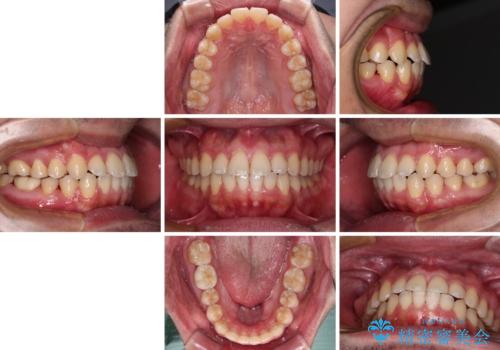

- 前歯のデコボコを治したいとのことで来院された患者様です。

できる限り楽して、短期間で治したいとのことで、ワイヤー装置にて矯正治療を行うこととしました。

インビザラインなどのマウスピース矯正は、楽に治療できると思われている方もいらっしゃると思いますが、毎日ストイックに22時間の装着を続けていくことは、決して楽なことではありません。

楽して治療したい方には、ワイヤー矯正がお勧めです。